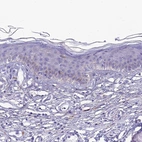

Immunohistochemistry analysis in human cerebral cortex and skeletal muscle tissues using HPA042754 antibody. Corresponding PRNP RNA-seq data are presented for the same tissues.